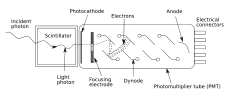

Scintillography is an imaging method of nuclear events provoked by collisions or charged current interactions among nuclear particles or ionizing radiation and atoms which result in a brief, localised pulse of electromagnetic radiation, usually in the visible light range (Cherenkov radiation). This pulse (scintillation) is usually detected and amplified by a photomultiplier or charge-coupled device elements, and its resulting electrical waveform is processed by computers to provide two- and three-dimensional images of a subject or region of interest.